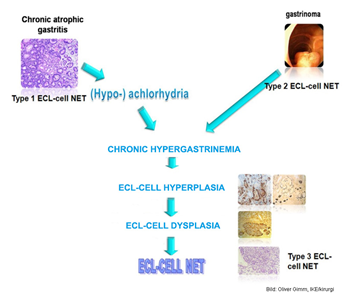

Vad vill denna grekiska bild förmedla?

- ECL:om typ 1 uppstår sekundärt till hypergastrinemi beroende på ex atrofisk gastrit, kan tas bort ganska enkelt och metastaserar sällan

- ECL:om typ 2 - associerade med Zollinger-Ellisons syndrom (gastrinproducerande tumör sm förekommer som delmanifestation vid MEN1) - behandlas som ovan)

- ECL:om typ 3 - sporadisk

Dessa kan producera histamin